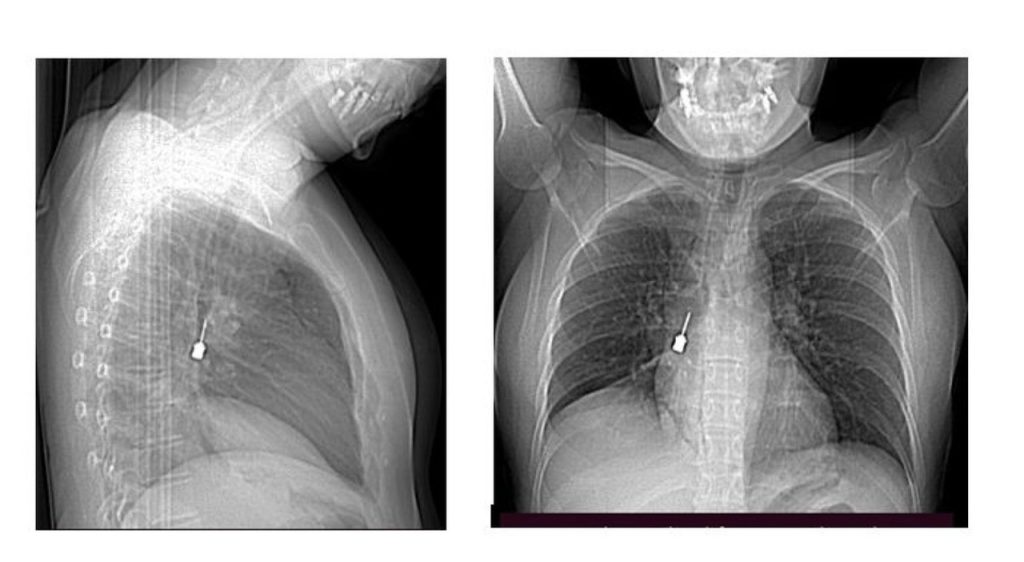

La paziente, allarmata dai sintomi e dalla crescente difficoltà respiratoria, ha deciso di sottoporsi a una Tomografia Computerizzata (TC) per determinare l’origine delle sue condizioni. L’esame ha messo in evidenza un corpo estraneo metallico posizionato nel bronco lobare inferiore del polmone destro, associato a un pneumomediastino, una condizione potenzialmente grave in cui si verifica la presenza di aria nello spazio compreso tra i polmoni.